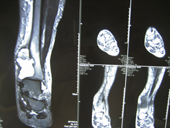

| Giant cell tumour MRI |

MRI2 |

MRI3 |